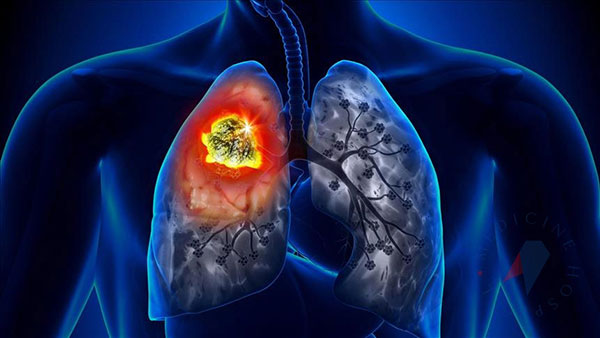

Akciğer vücudumuzun oksijen gereksinimini sağlayan organımızdır. Her organ gibi akciğerimiz de birçok hücreden oluşur. Bu hücreler akciğerin normal olarak görevini yapabilmesi için ihtiyaç doğrultusunda bölünerek çoğalırlar. Akciğer kanseri, yapısal olarak normal akciğer dokusundan olan hücrelerin ihtiyaç ve kontrol dışı çoğalarak akciğer içinde bir kitle (tümör) oluşturmasıdır. Burada oluşan kitle öncelikle bulunduğu ortamda büyür, daha ileriki aşamalarda ise çevre dokulara veya dolaşım yoluyla uzak oranlara yayılarak (karaciğer, kemik,beyin vb. gibi) hasara yol açarlar. Bu yayılmaya metastaz adı verilir.